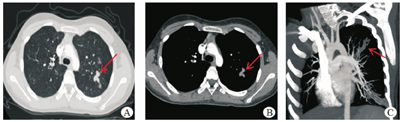

患者女,13岁,学生,因"反复咳嗽咳痰5个月,体检发现肝硬化1个月"于2019年2月14日收治我院。2018年9月,患者无明显诱因出现咳嗽咳黄痰,自行服用"感冒药"(具体不详),症状反复无缓解。病程中患者无腹胀不适,无低热盗汗,无腹痛,腹泻,二便正常,无明显体质量下降。患者既往史:2006年于南京儿童医院曾诊断为"巴特综合征",后好转;2018年发现鼻息肉,行摘除术。无既往感染病毒性肝炎、结核、血吸虫病史。无食物、药物过敏史。无手术外伤及输血史。患者祖母家族中兄弟四人有"肝硬化"病史,具体不详。2018年11月就诊于当地中医院予中药(具体不详)治疗3周,仍无明显缓解。2019年1月就诊于当地市级医院,超声及上腹部CT示肝硬化、胆囊结石、脾大;肺部CT示两肺散在条索状影及结节灶,左上肺见少许树芽征,查结核杆菌IgG阳性,痰结核菌及结核感染T细胞试验均阴性,诊断为:"肺结核,肝硬化原因不明",予利福平、异烟肼、吡嗪酰胺、乙胺丁醇抗结核治疗,咳嗽咳痰未见明显缓解,且肝硬化原因不明,遂来我院就诊。入院体格检查:神志清,精神可,发育正常,营养良好,皮肤黏膜无瘀点瘀斑,巩膜无黄染,未见肝掌、蜘蛛痣,浅表淋巴结未及肿大。双肺可闻及湿啰音,心律齐。腹软,无压痛及反跳痛,肝脾肋下未及,Murphy’s征阴性,肝区无叩痛,移动性浊音阴性,双下肢不肿,未见杵状指。血常规:白细胞8.28×109/L,中性粒细胞占比0.421,嗜酸性粒细胞占比0.160,嗜酸性粒细胞绝对值1.32×109/L;G试验254.60 pg/mL;肝功能:总胆红素6.2 μmol/L,白蛋白38.1 g/L,球蛋白23.7 g/L,丙氨酸转氨酶5.0 IU/L,天冬氨酸转氨酶16.4 IU/L,胆碱酯酶6 665 U/L,谷氨酰转肽酶25.9 U/L,碱性磷酸酶250.5 IU/L;肾功能、凝血功能未见异常,乙型肝炎表面抗原及甲型肝炎、丙型肝炎、戊型肝炎等病毒学指标均阴性,疫球蛋白、补体、自身免疫抗体、铜蓝蛋白测定等均未见明显异常。影像学检查:胸部CT平扫见两肺散在片状高密度影(图1);肝胆胰脾彩超示慢性肝损害、胆囊结石、脾轻度肿大;上腹部CT(平扫+增强)门静脉早显,增强动脉期肝内条片状强化稍高密度灶,考虑血管畸形或异常灌注;胆囊炎,胆囊结石;头部MRI提示副鼻窦炎。2月20日肝穿刺活检显示,肝小叶结构中-重度紊乱,小叶内肝细胞中度浊肿及多个点灶状坏死,部分融合成不规则片状,汇管区轻-中度扩张,轻-中度慢性炎细胞浸润及胶原纤维增生,可见汇管区-小叶间隔间及汇管区-汇管区间融合性坏死并轻度硬化,胆管数量较正常稍减少,可见局部轻度胆管炎(图2)。病变示活动性早期结节性肝硬化改变(G2~3/S3)。入院初步诊断为:"肺结核,待排查;肝硬化,原因待查;胆囊结石"。患者入院后,相关结果回报前,继续予利福喷丁联合异烟肼、吡嗪酰胺、乙胺丁醇、莫西沙星抗结核及抗感染治疗,患者咳嗽、咳痰症状无缓解,肺部湿啰音较明显。后结核相关检查结果示:痰抗酸杆菌、结核菌培养、结核感染T细胞试验、结核杆菌DNA/RNA均阴性。2月21日,患者行纤维气管镜检查示左肺上叶尖后段见较多黏稠分泌物,肺泡灌洗液抗酸杆菌阴性。2月27号,肺部CT提示两肺散在感染,较前进展,结核科会诊,相关检查及支气管镜结果不支持肺结核,遂停用抗结核药物;呼吸科会诊,血常规示嗜酸粒细胞比例及绝对值高,CT见支气管扩张,有"指套征",考虑变应性支气管肺曲霉病(ABPA)及嗜酸性粒细胞相关性肺炎可能,建议进一步完善血清总IgE及曲霉菌抗体检查,加用激素治疗。3月4日,予甲强龙30 mg治疗一周,患者咳嗽咳痰症状未见明显好转。3月11日,复查肺部CT示两肺感染,较前病灶范围略大,复查血常规:白细胞12.05×109/L,中性粒细胞占比0.580,嗜酸性粒细胞占比0.640,嗜酸性粒细胞绝对值0.77×109/L;曲霉菌抗体阴性。3月13日,再次行气管镜检查提示右肺中叶及左肺上叶支气管见较多黏液栓,予以抽吸及冲洗,进一步对肺泡灌洗液进行感染病原学基因检测,结果为烟曲霉阳性,确诊为ABPA。结合患者病史和临床特征,考虑"囊性纤维化(CF)病"。患者全外显子基因测序检出CFTR基因c.580-1G>T(剪接突变,致病性)和c.1000C>T(p.Arg334Trp错义突变,致病性)复合杂合突变,两个突变位点分别来自其父亲及母亲,遂患者确诊为囊性纤维化。予甲强龙30 mg/d,联合伏立康唑200 mg,12 h/次治疗3周,患者咳嗽咳痰症状消失,肺部湿啰音消失,肺部CT病灶明显减少,G试验138.00 pg/mL,肝功能正常,患者好转出院。2019年4月当地复查胸部CT炎症明显吸收。

注:A、B、C分别为肺窗、纵膈窗及最大密度投影重建图像。箭头所示为明显扩张的支气管内黏液栓阻塞,增强后未见扩张支气管及粘液栓未见强化,呈"指套征"改变